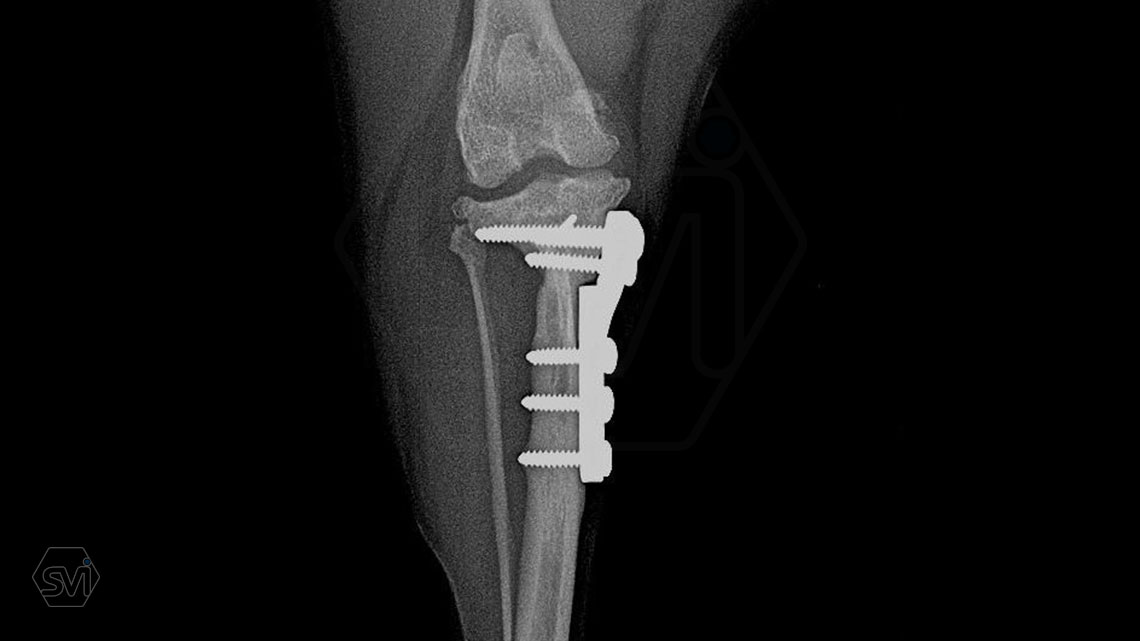

What used to be a nightmare type of surgery is slowly becoming my favorite: the humerus distal Y fracture